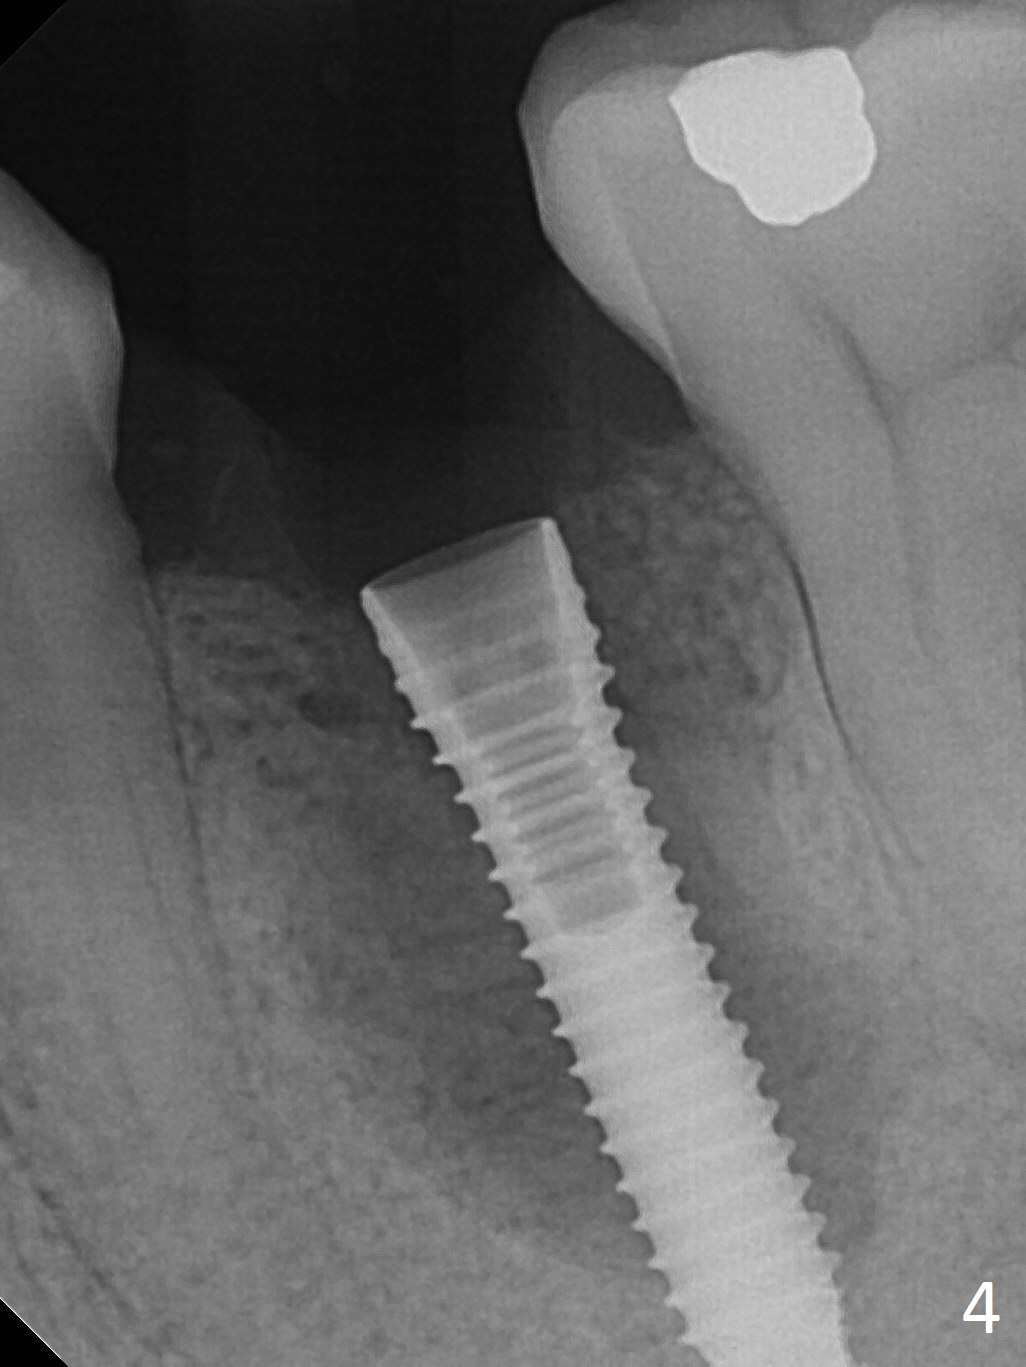

Extraction of the lower left 2nd premolar with vertical fracture (Fig.1,2 >) is easy because of peri-radicular radiolucency.  The apical end of the osteotomy is not shown with a 2 mm pilot drill (Fig.3) or a 3.8x18 mm implant (Fig.4) in place.  It appears that the implant is not placed deep enough.  Following 3-4 more turns of the implant and placement of a 5.5x4(3) mm abutment (Fig.5 A), allograft is placed (*).  A postop panoramic X-ray is taken (Fig.6); the osteotomy could have been deepened to reduce the possibility of periimplantitis.  Retrospectively, the panoramic X-ray should be taken after use of the pilot drill. The bone around the implant appears to have regenerated 4 months postop (Fig.7,8).  Bone density appears to continue increasing 9 months postop (i.e., 4.5 months post cementation, Fig.9).  Bone loss is minimal 2 years post cementation (Fig.10).